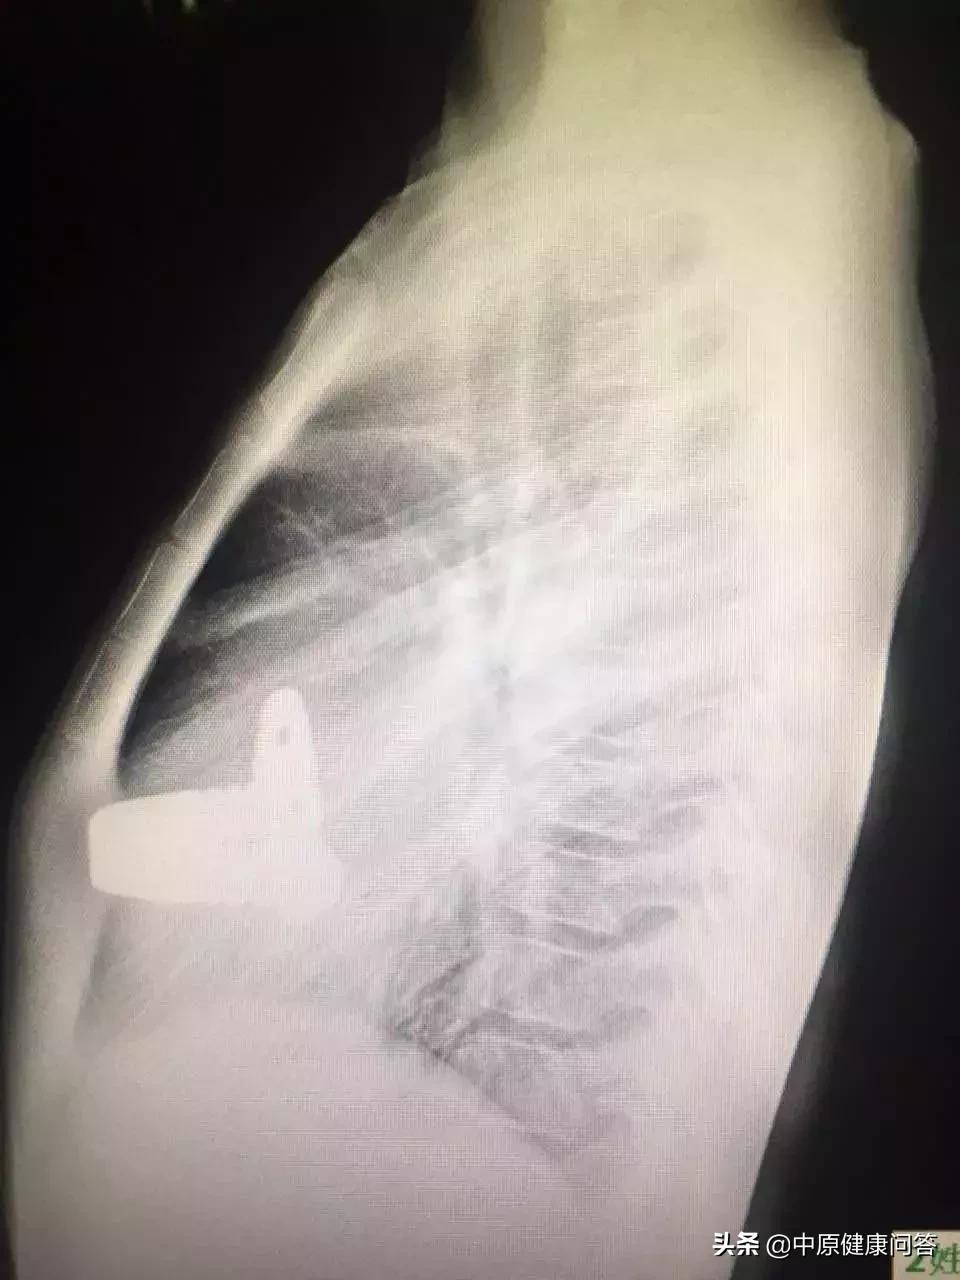

术后2年11月胸部侧位片显示胸骨已挺起